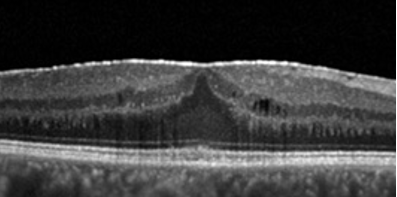

membrana epirretiniana distorcendo o contorno macular

síndrome de tração vítreo-retiniana